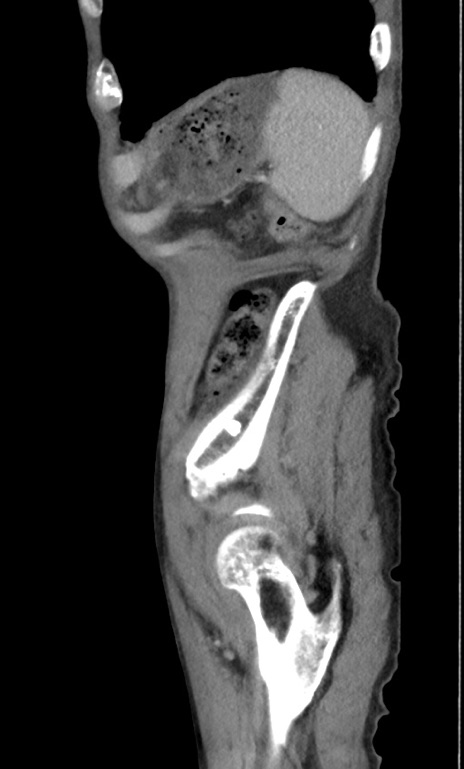

症例3(矢状断像)

【症例】 70歳代男性

【主訴】右鼠径部腫瘤、疼痛

【現病歴】本日朝より上記主訴あり、受診。

【既往歴】膀胱癌にて膀胱全摘、両側尿管皮膚瘻

【データ】WBC 5600、CRP 0.56